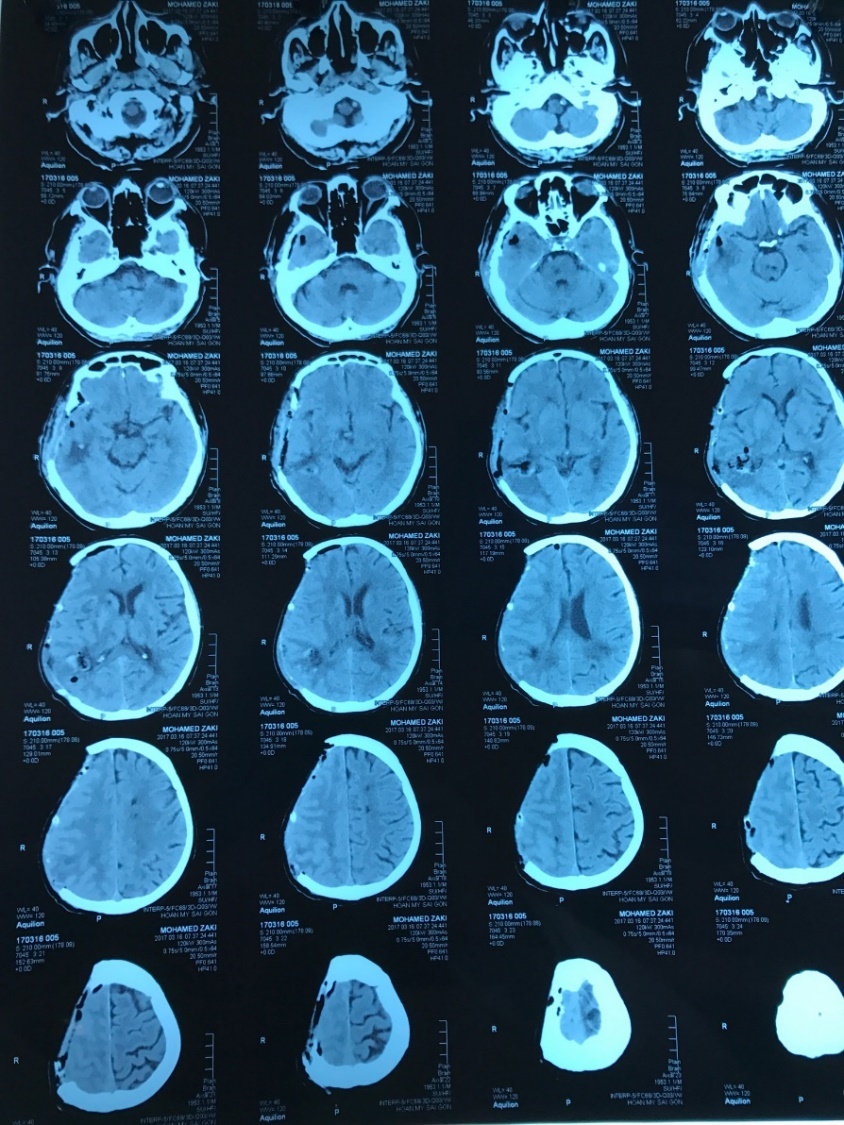

Với tình trạng yếu nửa người và hôn mê trong tiên lượng rất xấu, bệnh nhân được đưa vào khoa cấp cứu tại Bệnh viện Hoàn Mỹ Sài Gòn lúc nửa đêm. Nguyên nhân xác định ban đầu là xuất huyết não, có nguy cơ biến chứng phức tạp, thậm chí tử vong. Sau hội chẩn khẩn cấp, bệnh nhân được thực hiện chụp cắt lớp vi tính (chụp CT) có bơm thuốc xác định chính xác nguyên nhân nhằm tìm phương án mổ tối ưu.

| Phim chụp cắt lớp của bệnh nhân M.

Trước phẫu thuật, bệnh nhân M ở tình trạng xuất huyết não nghiêm trọng, phù não với lượng máu tụ lớn. Ca mổ với mục tiêu giải phóng áp lực cho não yêu cầu đường mổ đủ lớn, đồng nghĩa với nguy cơ biến chứng sau mổ phức tạp.